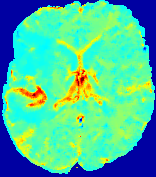

LesionRefer to captionRefer to captionRefer to captionRefer to captionRefer to captionRefer to caption𝐕rgbsubscript𝐕𝑟𝑔𝑏{\bf{V}}_{rgb}Refer to captionRefer to captionRefer to captionRefer to captionRefer to captionRefer to caption𝐕2subscriptnorm𝐕2{\|\bf{V}}\|_{2}Refer to captionRefer to captionRefer to captionRefer to captionRefer to captionRefer to captionRefer to caption3.53.53.52.82.82.82.12.12.11.41.41.40.70.70.70.00.00.0(mm/s)𝑚𝑚𝑠(mm/s)D𝐷DRefer to captionRefer to captionRefer to captionRefer to captionRefer to captionRefer to captionRefer to caption0.0200.0200.0200.0160.0160.0160.0120.0120.0120.0080.0080.0080.0040.0040.0040.0000.0000.000(mm2/s)𝑚superscript𝑚2𝑠(mm^{2}/s)Slice #1Slice #2Slice #3Slice #4Slice #5Slice #6

Figure 4: PIANO feature maps for another patient in the ISLES 2017 training set, where the lesion is located in the right hemisphere. Top row: segmented stroke lesion region (white) on different slices. The corresponding slices for the PIANO feature maps are shown in the following rows.

For a better insight into an estimated velocity field 𝐕𝐕{\bf{V}} and diffusion field 𝐃𝐃{\bf{D}}, we compute the following maps: (1) 𝐕rgbsubscript𝐕𝑟𝑔𝑏{\bf{V}}_{rgb}: Color-coded orientation map of 𝐕=(Vx,Vy,Vz)T𝐕superscriptsuperscript𝑉𝑥superscript𝑉𝑦superscript𝑉𝑧𝑇{\bf{V}}=(V^{x},V^{y},V^{z})^{T}, obtained by normalizing 𝐕𝐕{\bf{V}} to unit length and mapping its 3 components to red, green, blue respectively; (2) 𝐕2subscriptnorm𝐕2\|{\bf{V}}\|_{2}: 222 norm of 𝐕𝐕{\bf{V}}; (3) D𝐷D: scalar field in Eq. 5.

Fig. 3 and Fig. 4 show the PIANO feature maps estimated from two ISLES 2017 patients: all are highly consistent with the lesion in both cases. Details of the blood flow trajectories are revealed in 𝐕rgbsubscript𝐕𝑟𝑔𝑏{\bf{V}}_{rgb} by the ridged patterns and the sharp changes of colors in the unaffected (right) hemisphere, while the flat patterns appearing within the lesion provide little directional information about the velocity and indicate low velocity magnitudes. Velocity magnitudes are more directly visualized via 𝐕2subscriptnorm𝐕2\|{\bf{V}}\|_{2}, from which one can easily locate the lesion where 𝐕2subscriptnorm𝐕2\|{\bf{V}}\|_{2} is low. D𝐷D also indicates lower diffusion values in the lesion, though with less contrast potentially due to the fact that it captures the accumulated effect of CA diffusion at the voxel-level.